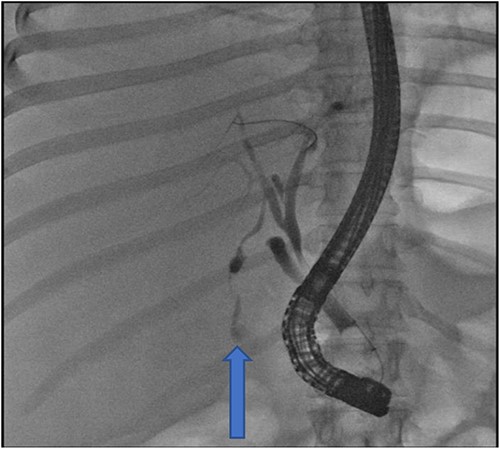

At our facility, ERCP was done. The bile duct was cannulated with 0.035 wire-guided sphincterotome. Cholangiogram showed normal caliber biliary tree with one filling defect in the distal CBD and contrast leak from duct of Luschka to the gall bladder bed (Fig. 1). There was no contrast leak from the cystic duct stump (Fig. 2A). Standard sphincterotomy was performed and a single mulberry stone was removed using stone retreival balloon and double pig tail biliary plastic stent was placed into the RHD and good bile flow was achieved post procedure (Fig. 2B).

Fluoroscopy image indicating bile leak from type 2 duct of Luschka.